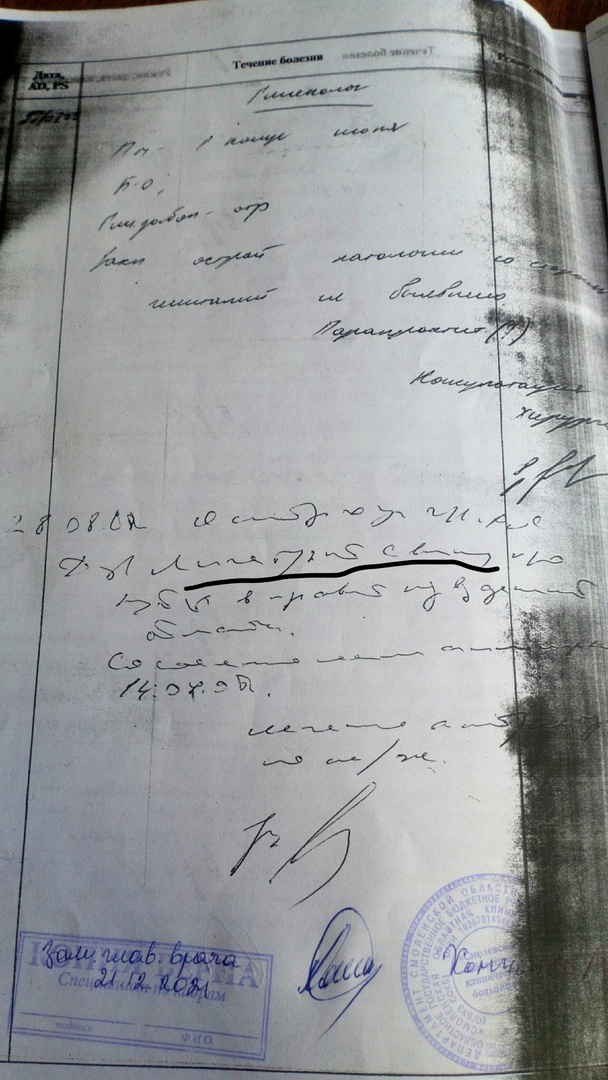

В 2008 году, как рассказывает смолянка, ей провели операцию по устранению аппендицита. Процедура в областной больнице длилась около трех часов, что, по меркам хирургии, сравнительно долго. При этом после мероприятий антибиотики порекомендовали вообще не пить из-за аллергии.

— Операция проводилась на пятый день после начала симптомов — в местной ЦРБ аппендицит не смогли обнаружить, не провели УЗИ — аппарат был сломан. Лечащий врач в областной игнорировал симптомы и мнение коллег, которые говорили о повторной полостной операции через двое суток после удаления аппендикса, потом вообще стал угрожать вызовом психиатра, — отмечает девушка в сообществе «Подслушано Смоленск».

Новообразование так и не иссекли и смолянка до 2020 года ходила с постоянной температурой и болью. Кроме того, девушка похудела на 15 килограмм. Обращение в Железнодорожную больницу дало небольшой результат — пациентке рассказали, что все это время она живет с постаппендэктомическим инфильтратом, то есть скоплениями крови и лимфы в месте прошлой операции.